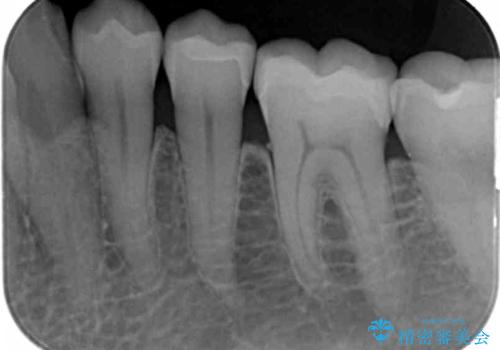

銀歯を外してのセラミック治療

- 長年見た目が気になっていた銀歯のやりかえを希望されて来院されました。

銀歯を丁寧に除去し、セラミクインレーによる置き換えを行いました。

セラミックインレーの治療に際しては、拡大鏡を用いた丁寧な除去・形成、シリコン印象材による精密な型取りを行い、虫歯の再発を防ぐような精密修復を実践していきます。